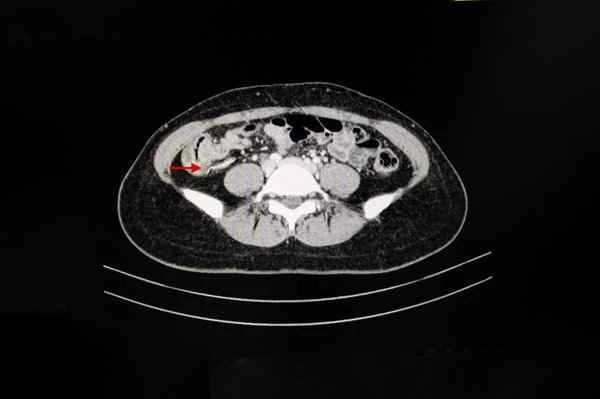

Appendiceal mucinous tumors are tumors originating from cells within the wall of the appendix that produce mucus. These tumors can be classified into several types, including appendiceal mucinous cystadenoma and appendiceal mucinous cystadenocarcinoma. The cellular morphology and tissue structure of these tumors help doctors determine their malignancy. Tumors are defined as cancerous only when they exhibit high atypia, aggressive growth, or distant metastasis.